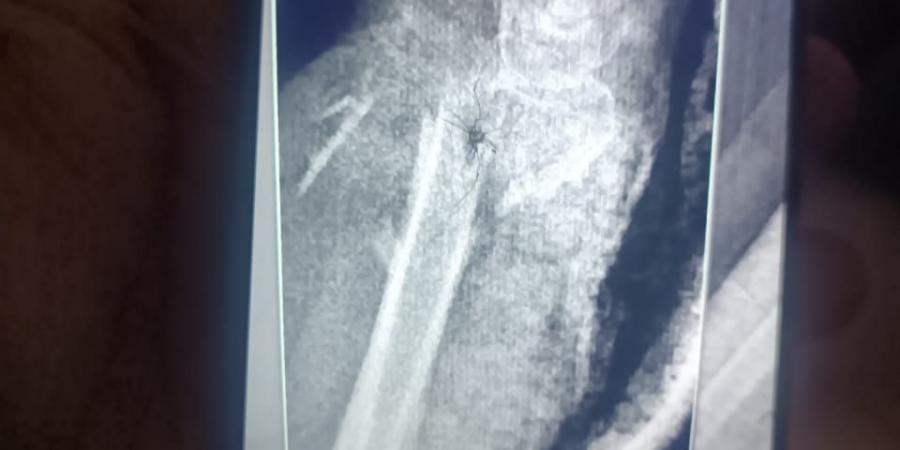

وأكدت الدكتورة نيفين شعبان، وكيل وزارة الصحة بالفيوم، أن مستشفى الفيوم العام، بقيادة الدكتور محمد عبد الله، استقبلت الحالة وهي تعاني من تهتك شديد بالجلد، وقطع كامل بالأعصاب والأوتار في منطقة الرسغ، مع تأثر بالغ بالدورة الدموية لليد، نتيجة كسر مضاعف بعظام الساعد، ما شكّل تهديدًا حقيقيًا بفقدان اليد.

وبدأ التدخل الجراحي بقيام فريق جراحة العظام بتثبيت الكسر المضاعف بدقة عالية، لضمان استقرار العظام وتهيئة الحالة لاستكمال التدخل الجراحي الدقيق.